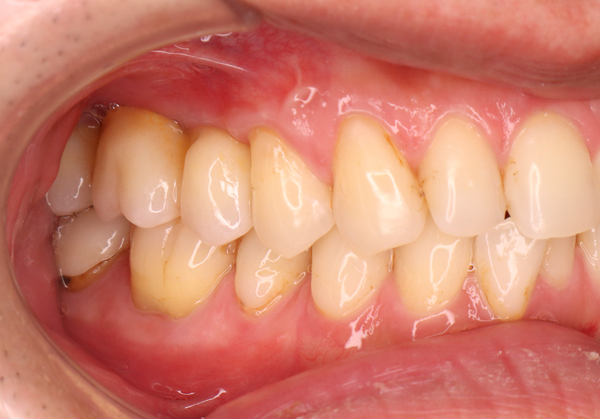

治療の経緯

右上の歯が取れたので、噛めるようにしたい

治療方法

奥歯は歯根破折していたため、抜歯をし、骨が少なかったため上顎洞にサイナスリフトを行い、骨を補填してインプラントを埋入しました。インプラントブリッジにて被せ物を作りました。

治療期間 動的期間6ヶ月

費用 インプラント埋入2本 600,000円

サイナスリフト  330,000円

セラミックのブリッジ(クラウン3本分)  450,000円

合計   1,380,000円

治療によるリスク インプラントは歯周病に弱いため、歯周病にかかると悪化する可能性があります